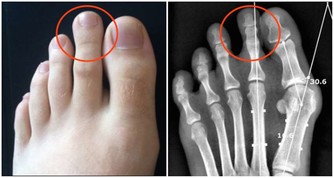

莧菜平衡酸鹼值,補血又使痛風消。莧菜有紅莧、白莧,應該大量推廣。

尿酸痛風的人,可以每天吃一碗莧菜湯,或像我們客家人用莧菜煮麵線,但是不要放吻仔魚。

莧菜能平衡酸鹼,你的尿酸痛風就會好。

不要吃冰的東西,不要吃香蕉,香蕉吃了痛風就發作,因為裡面有鉀離子。